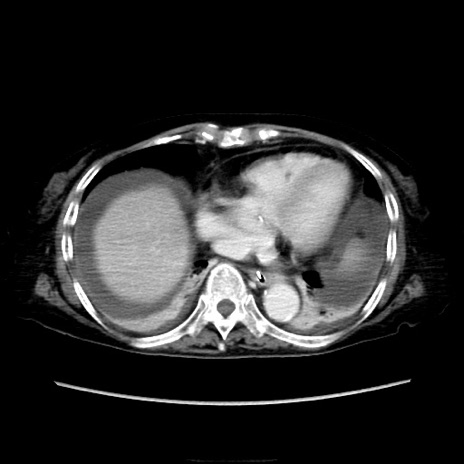

症例40(横断像)

横断像